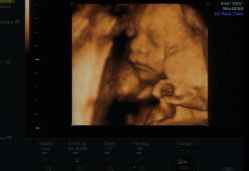

• -郑州万安妇产医院

相册

小仙女就是Me 上传于 19-01-08 | 报错